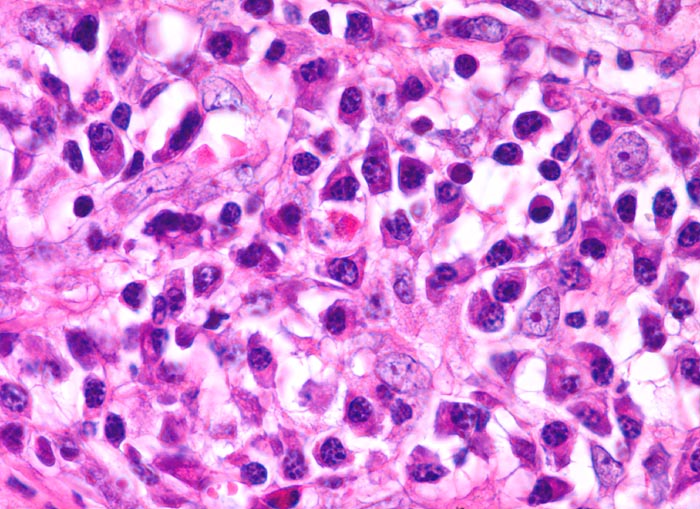

PathoPic ID 3878 - Hodgkin-Lymphom, reaktives gemischtes Zellinfiltrat

Hodgkin-Lymphom, reaktives gemischtes Zellinfiltrat

maligner Tumor

Lymphknoten, mediastinal

Lymphatische Gewebe, KM, Milz

Mischzellinfiltrat aus reaktiven, nicht-malignen Zellen wechselnder Zusammensetzung: Lymphozyten,

Histiozyten, eosinophile Granulozyten, zahlreiche

Plasmazellen.

Hodgkin Lymphom, noduläre Sklerose

Mediastinaler Tumorbulk.

630

21